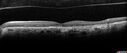

Geographic Atrophy with Vision Change

80 year old female Recent vision loss in the left eye for about 6 weeks.

VA 20/25 OD, 20/63 OS (was 20/40 5/3/21 at patients first visit)